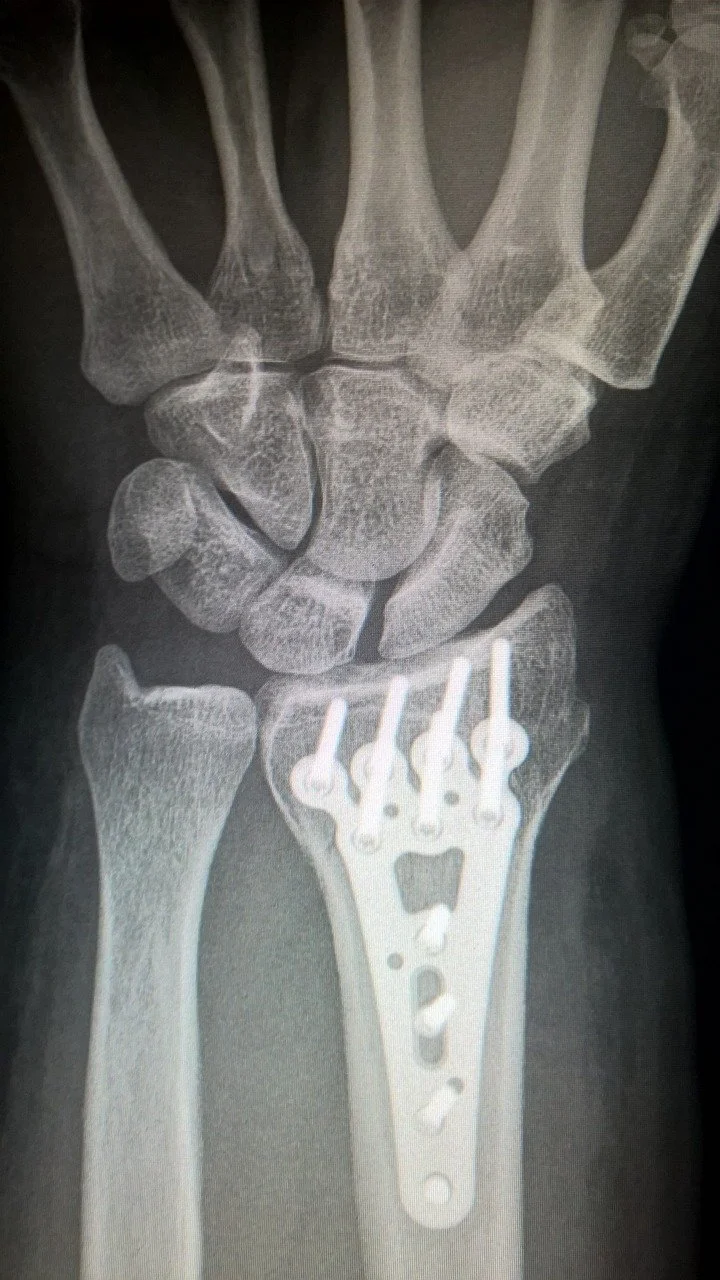

The Break Is Just the Beginning

After a fracture, the first stop is often the ER or urgent care. But that’s rarely where treatment should end — especially for wrist fractures, ankle breaks, shoulder injuries, or hip trauma.

In Circleville, too many patients are left with vague follow-up instructions and unclear timelines.

That’s where we come in.

Why Follow-Up Orthopedic Care Matters

Improper healing can lead to:

• Long-term stiffness or pain

• Malunion (bone heals in the wrong position)

• Nonunion (bone doesn’t heal at all)

• Weakness, deformity, or permanent loss of motion

That’s why timing and expertise matter.

When to See an Orthopedic Surgeon

If you’ve been diagnosed with a fracture and have:

• Ongoing swelling or pain

• Delayed healing

• A displaced break that might need surgery

• A cast or splint but no clear treatment plan

You’re not being difficult. You’re being smart. You deserve orthopedic follow-through.